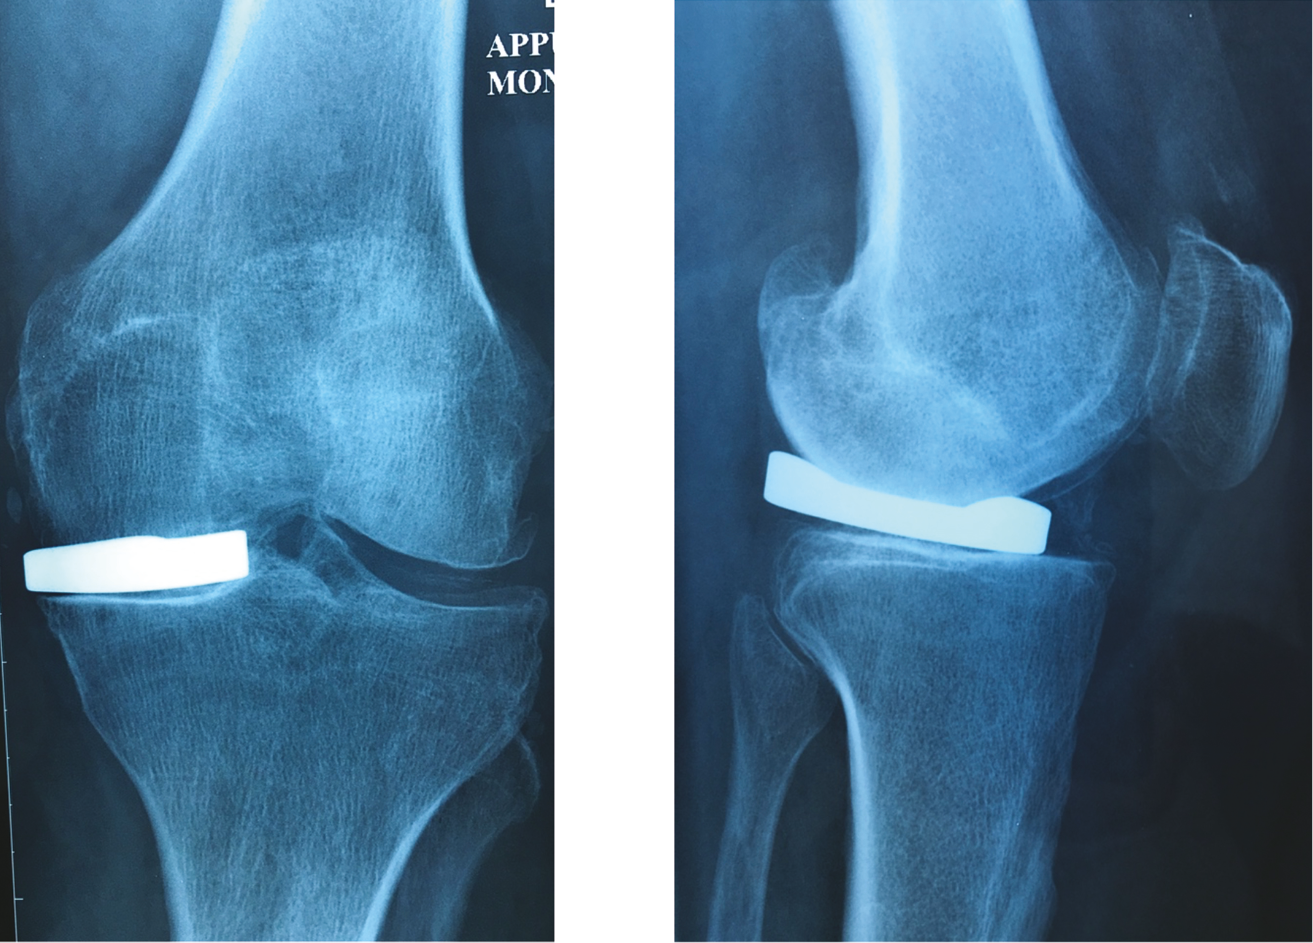

At 15 years, the clinical results for the Oxford 3 were excellent, [58] H. Pandit, T. Hamilton, C. Jenkins, S. Mellon, C. Dodd, D. Murray “The Clinical Outcome of Minimally Invasive Phase 3 Oxford Unicompartmental Knee Arthroplasty: A 15-Year Follow-up of 1000 UKAs,” The Bone & Joint Journal. 2015; 97B: 1493–1500 confirming the findings of Price & Svard [59] A. Price, U. Svard. A second decade lifetable survival analysis of the Oxford uni-compartmental knee arthroplasty. Clin Orthop Relat Res. 2011; 469:174–179. and Liddle [60] A. Liddle, A. Judge, H. Pandit, D. Murray. Determinants of revision and functional outcome following unicompartmental knee replacement. Osteoarthritis Cartilage. 2014 ; 22 :1241–1250. who had recorded 92% implant survival at 20 years for the Phase 1 and 2 Oxford models (Figs. 17 & 18).